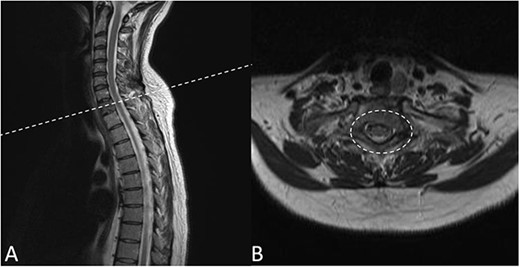

Preoperative magnetic resonance imaging (MRI) and preoperative CT scans helped determine Tokuhashi, Tomita and ESCC scores, which was vital to plan treatment for this patient (Figs 1 and 2). The occurrence of the lesion occurring in T2 indicated an anterior approach. This would be safer than a posterior approach as the ESCC grade of 2 made it surgically challenging to resect tumour and lay instrumentation around the spinal cord. An anterior approach also avoids cervico–thoracic junction fusion.

Preoperative CT Scan December 2019. Sagittal view of oligometastatic lesion at T2 vertebral body. (A) Sagittal view of oligometastatic lesion at T2 vertebral body. (B) Transverse view determined ESCC grade 2 as there is spinal cord compression, but with cerebrospinal fluid visible around the cord.